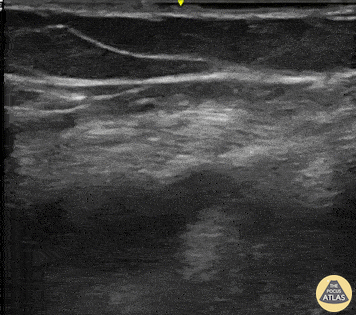

What is the sign shown in this lung scan:

Lung Point